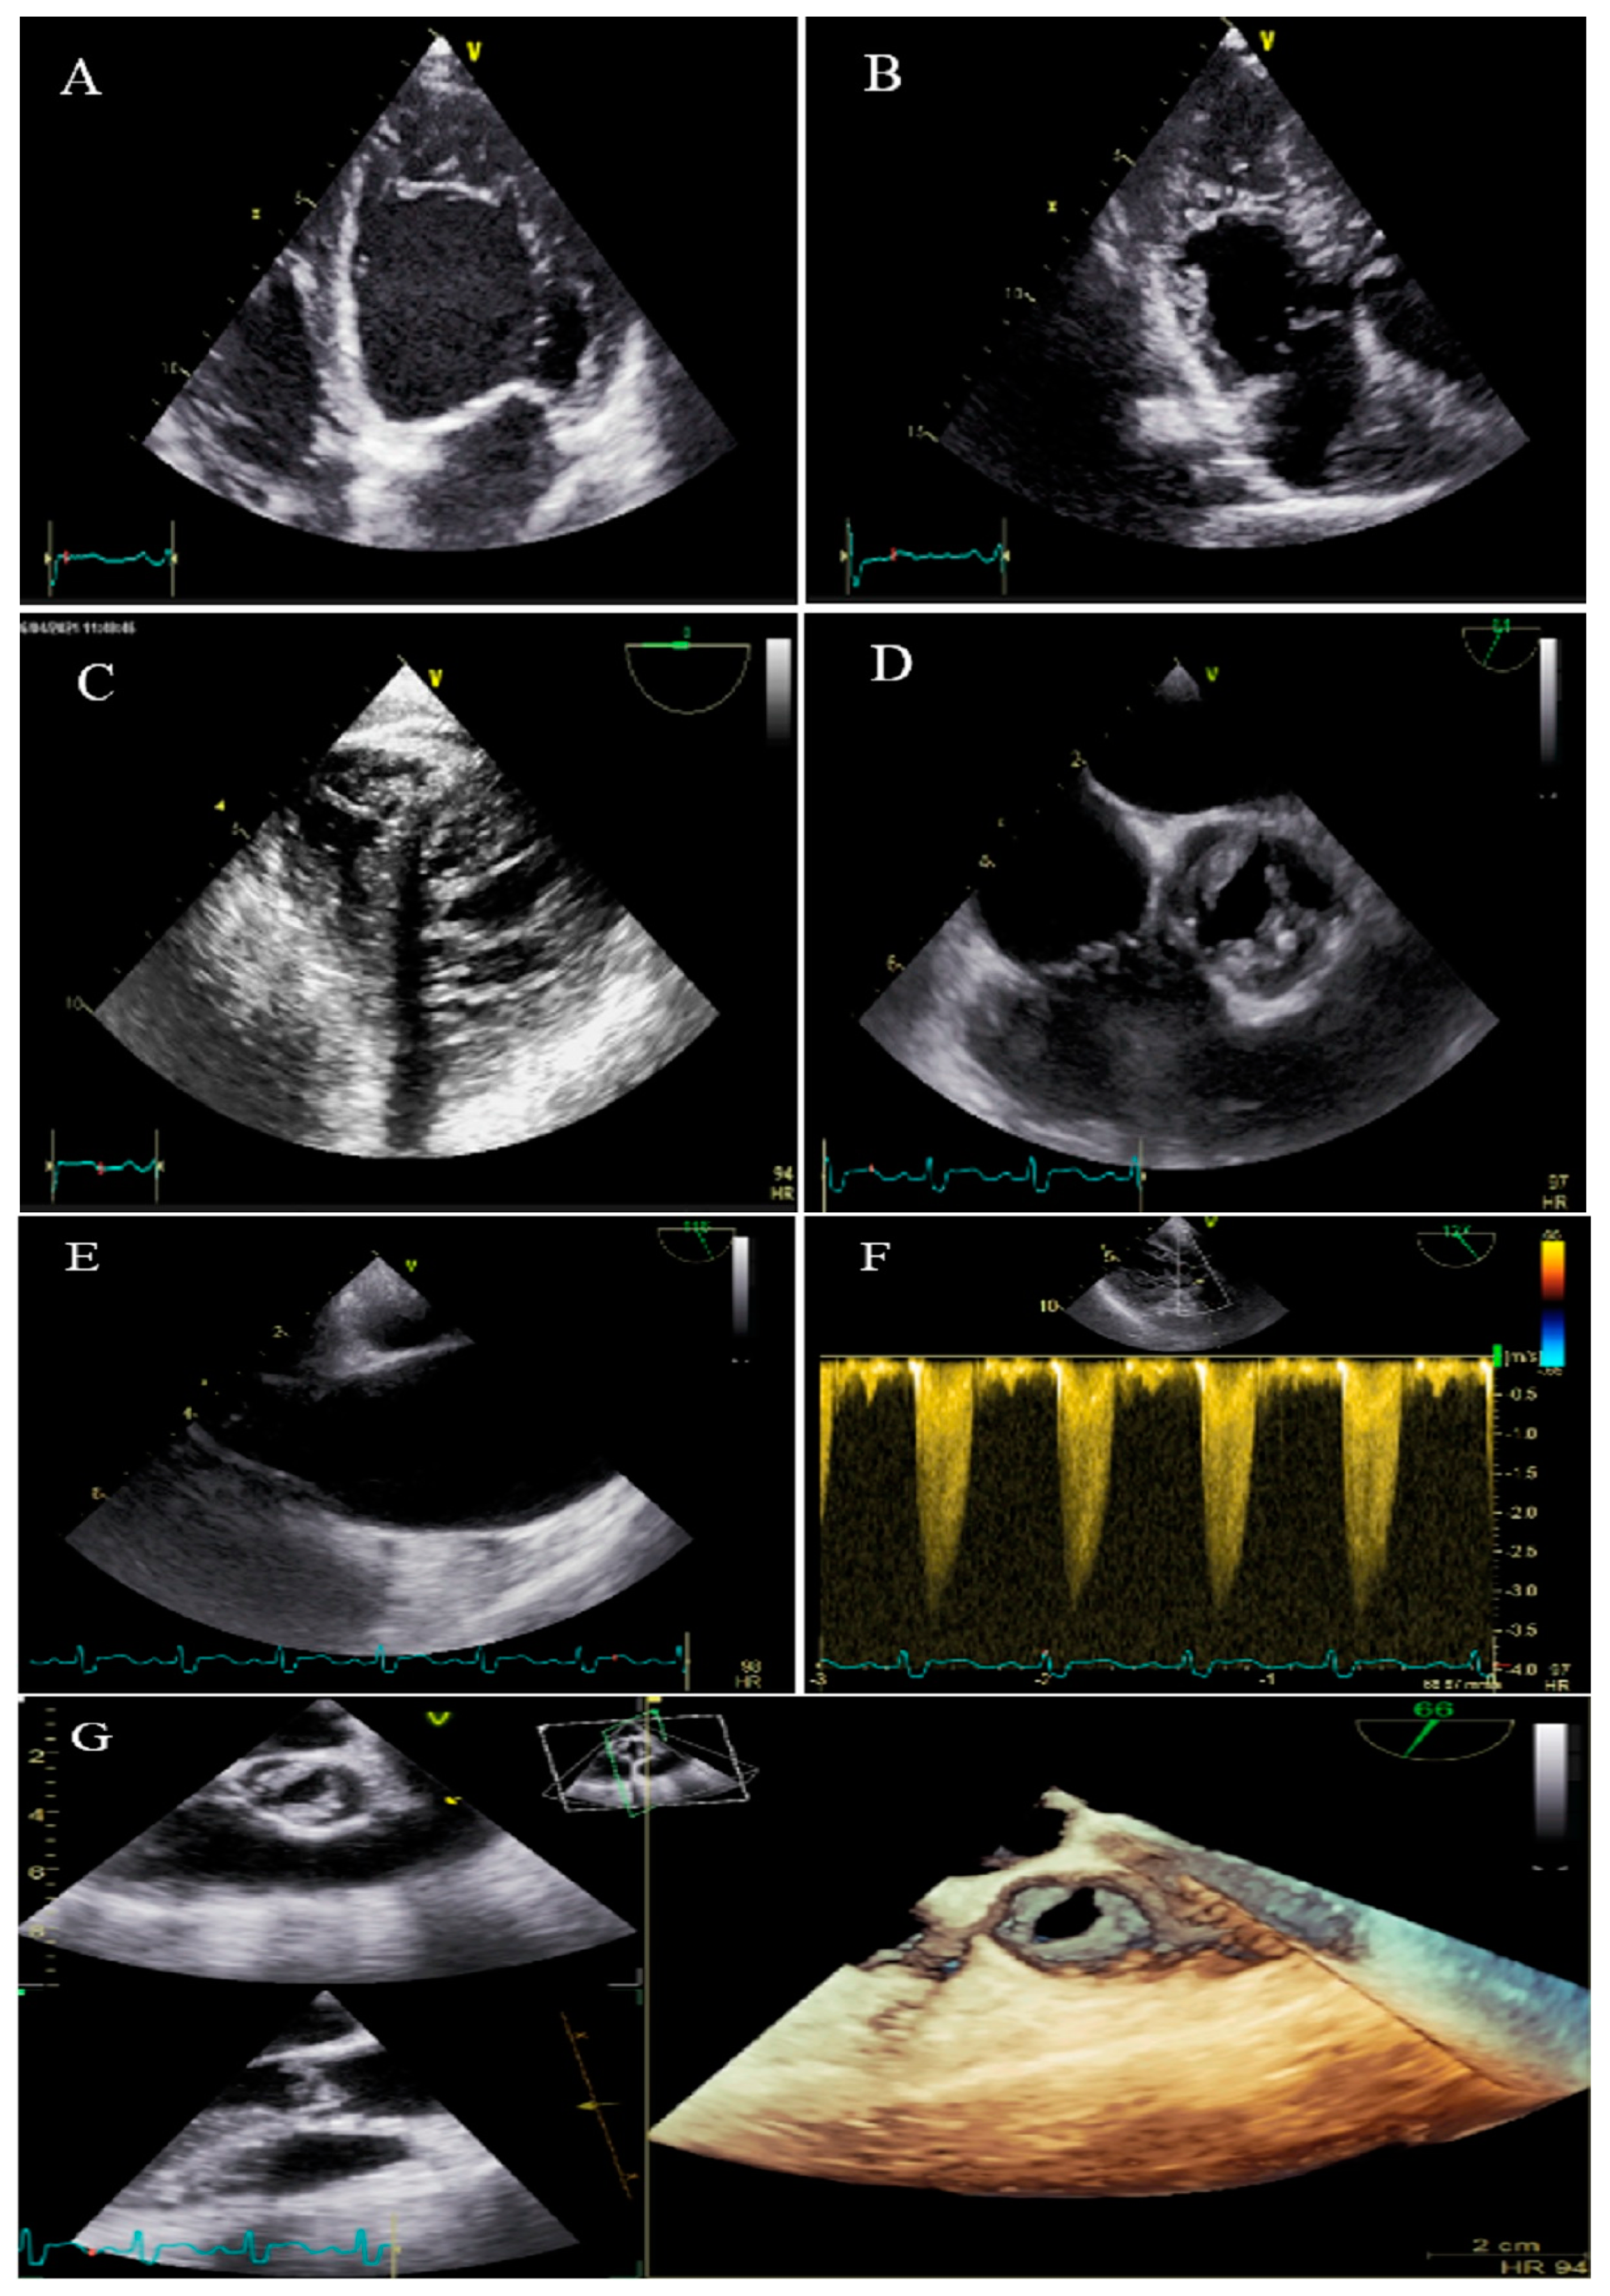

2.7. Case #7. BVNC, BAV, AS, and Dilated Aorta Ascending Aorta

| 7 | M | 48 | Dyspnea on moderate exercise and easy fatigability for six months | − | BVNC, LVEF = 55% | BVNC, BAV, aortic stenosis, and dilated ascending aorta | + | Denied because of claustrophobia | Spironolactone 25 mg, carvedilol 12.5 mg daily | Doing well 2 months later. He did not return for a follow-up |